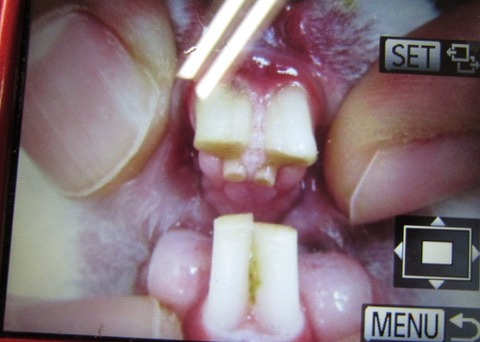

6月8日、かぐらちゃんの切歯定期通院でした。

パっ見、伸びてるように感じませんが…

きちんと見ると、きちんと伸びてるんですね…

処置後

ちょっと割れちゃいました